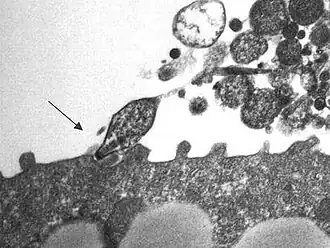

Mycoplasma pneumoniae é uma das menores bactérias conhecidas pelo ser humano. É causadora da pneumonia por Mycoplasma, um tipo de pneumonia bacteriana. Este microorganismo pode apenas sobreviver como parasita em outras células.[1]